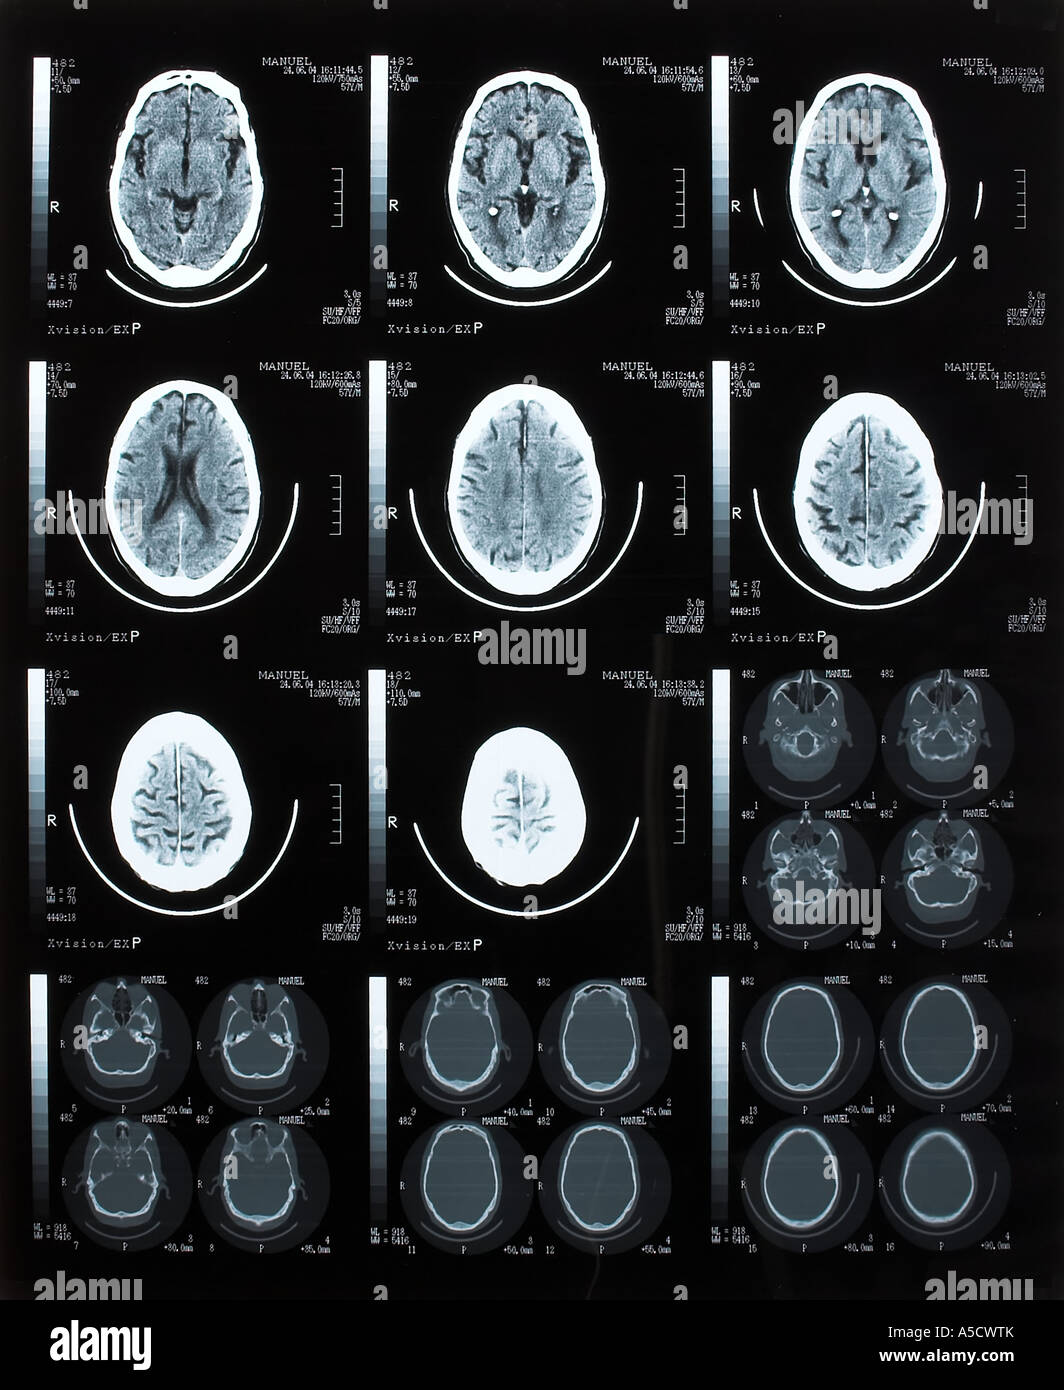

Tomodensitométrie cérébrale Banque D'Imageshttps://www.alamyimages.fr/image-license-details/?v=1https://www.alamyimages.fr/photo-image-tomodensitometrie-cerebrale-11273199.html

Tomodensitométrie cérébrale Banque D'Imageshttps://www.alamyimages.fr/image-license-details/?v=1https://www.alamyimages.fr/photo-image-tomodensitometrie-cerebrale-11273199.htmlRFA5CWTG–Tomodensitométrie cérébrale

Tomodensitométrie cérébrale Banque D'Imageshttps://www.alamyimages.fr/image-license-details/?v=1https://www.alamyimages.fr/photo-image-tomodensitometrie-cerebrale-11273202.html

Tomodensitométrie cérébrale Banque D'Imageshttps://www.alamyimages.fr/image-license-details/?v=1https://www.alamyimages.fr/photo-image-tomodensitometrie-cerebrale-11273202.htmlRFA5CWTK–Tomodensitométrie cérébrale

Tomodensitométrie cérébrale Banque D'Imageshttps://www.alamyimages.fr/image-license-details/?v=1https://www.alamyimages.fr/photo-image-tomodensitometrie-cerebrale-12412994.html

Tomodensitométrie cérébrale Banque D'Imageshttps://www.alamyimages.fr/image-license-details/?v=1https://www.alamyimages.fr/photo-image-tomodensitometrie-cerebrale-12412994.htmlRFA9P22Y–Tomodensitométrie cérébrale